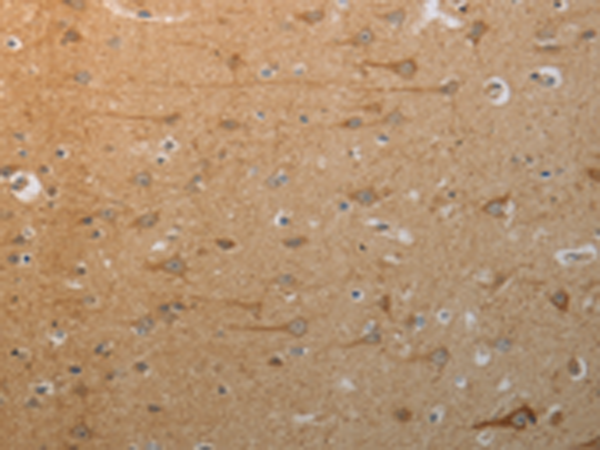

分类: 科研抗体货号: P04152别名: GLUH1; GLUR1; GLURA; GluA1; HBGR1应用: WB,IHC反应种属: Human, Mouse, Rat